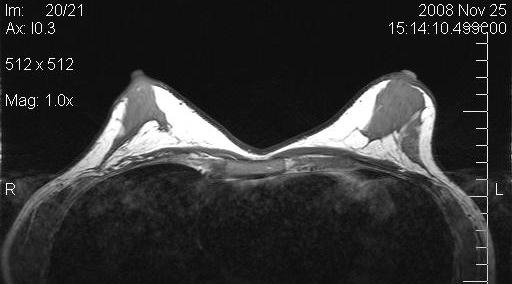

Figure 10 [Fig. 10] and Figure 11 [Fig. 11] show the MRIs of a patient pre- and postoperatively.

Figure 11: Postoperative MRI of the same patient after implant removal and subsequent fat grafting

Magnetic resonance imaging (MRI) of the breasts was performed in 5 patients preoperatively and 6 months postoperatively. The evaluation by MRI based volumetry gave inconsistent results, presumably due to the fact that volume (the implant) is first removed, and then added by fat grafting in one procedure. Also, the form of the preoperatively often very tight breasts changed dramatically. All MRI showed massive increase in fat tissue. No cysts were observerd.

The next two images show the preoperative and postoperative MRI scans of the patient of Figure 6 [Fig. 6] with capsular fibrosis after complete subpectoral placement (Figure 12 [Fig. 12], pre-op), and after implant removal and fat grafting (Figure 13 [Fig. 13], post-op). Remainders of the capsule are not to be seen after the procedure. The amount of fat grafted was only 2/3 of the implant volume. The patient was extremely pleased with the result and did not wish further volume increase.